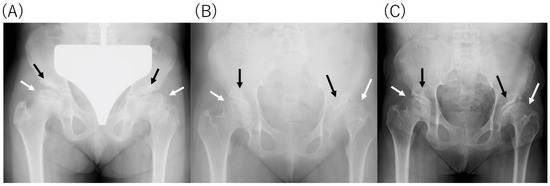

2.4. Radiological Findings